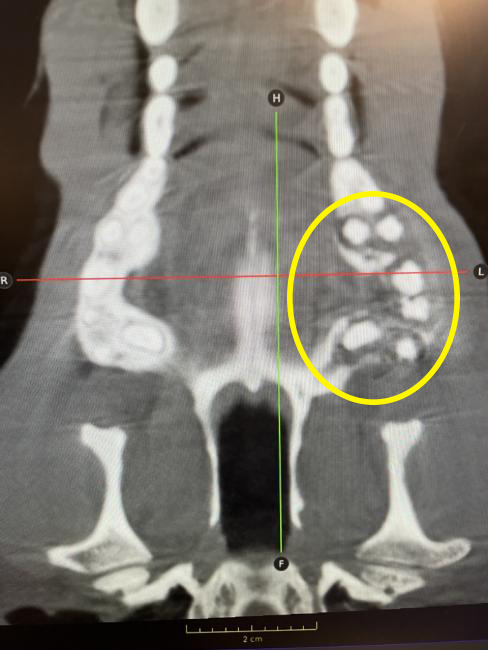

Standiford Veterinary Center strives to provide our patients with the highest level of care. One of the many advanced medical services provided is Computed Tomography or CT scan. CT takes numerous thin “slices” (or X-rays) of the area of interest and then reconstructs the data mathematically into a highly sophisticated and detailed 3-D representation. This scan can be rotated allowing the bones, soft tissue, and vascular structures to be isolated and individually evaluated. Contrast media can be included to markedly improve imaging accuracy and sensitivity.

Most patients are referred for advanced CT imaging when routine diagnostics such as ultrasound or radiographs cannot accurately provide the information needed for a diagnosis or prognosis. CT is exceptional in detecting changes in bones, joints, and cavities or sinuses in the head including the inner ear. The CT also visualizes the spine, chest, lungs, and abdomen. Again contrast agents can provide a detailed map of the blood flow to particular areas such as the liver.